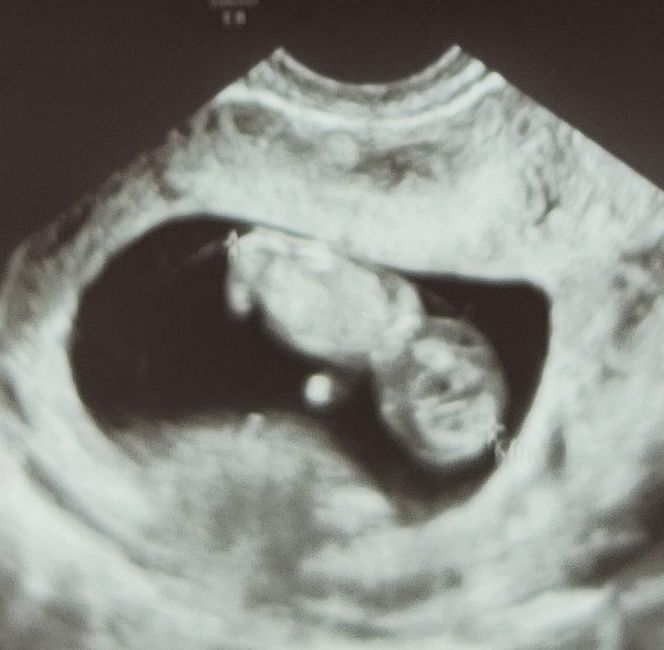

Hola chicas, mi bebé arcoiris… mi eco de hoy via vaginal. En verdad me da igual el sexo, solo quiero que venga san@ pero me da curiosidad el metodo jejej

Método Ramzi 3